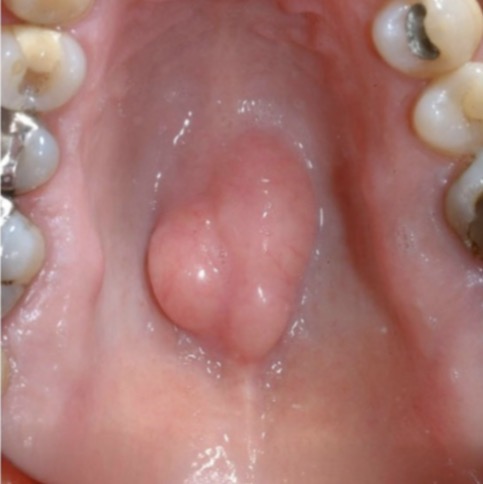

Condition?

Torus palantinus

What is the most likely cause for the redness on this torus?

Trauma